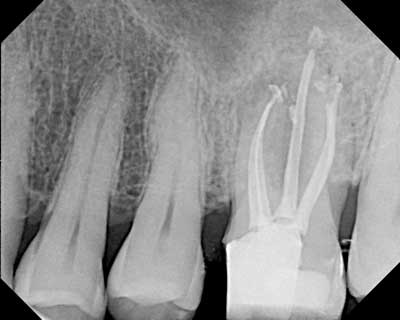

Fig. 1 — Clinical case instrumented with Twisted Files* and obturated with RealSeal One Bonded Obturators.*